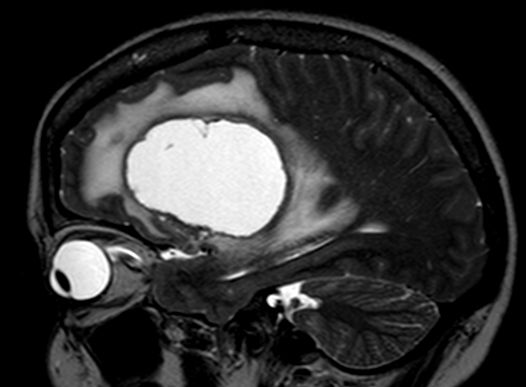

| große zystische Hirnmetastase | asymptomatisches Adenokarzinom des linken

Hauptbronchus mit primärer Hirnmetastase![]() ![]() |